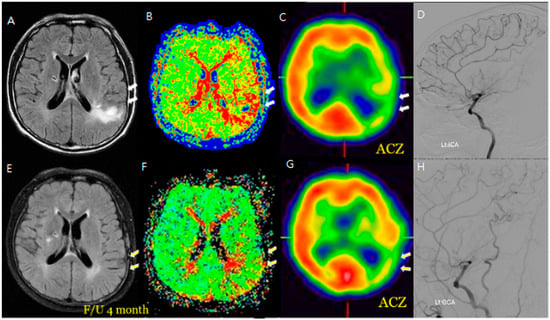

Additionally, changes in the ivy sign on MR FLAIR images were compared with MR perfusion images. The degree of change in mean transit time (MTT) was greater in areas with positive or minimal HV compared to areas with negative HV. After STA-MCA bypass surgery, regions where HV decreased or disappeared showed improved hemodynamics, as reflected in both SPECT and MR perfusion imaging (Figure 2), and this correlation between HV regression and improved cerebral perfusion was similarly observed in a patient with distal ICA stenosis (Figure 3).

Figure 2. An M/58 symptomatic steno-occlusive patient (Rt. hemiparesis with Lt. M1 occlusion). Preoperative MR FLAIR, perfusion MR, and SPECT (AD) show hyperintense vessels, indicating a decreased cerebral vascular reserve; a postoperative decrease or absence of hyperintense vessels reveals successful revascularization for decreasing HV after F/U; and a decrease in HV on the bypass-established hemisphere is associated with an improved hemodynamic status (EH). Hyperintense vessels in preoperative FLAIR (A) coincide with a perfusion delay on SPECT (C). Postoperatively (EH), the HV resolution matches with improved perfusion, demonstrating spatial and functional improvement.